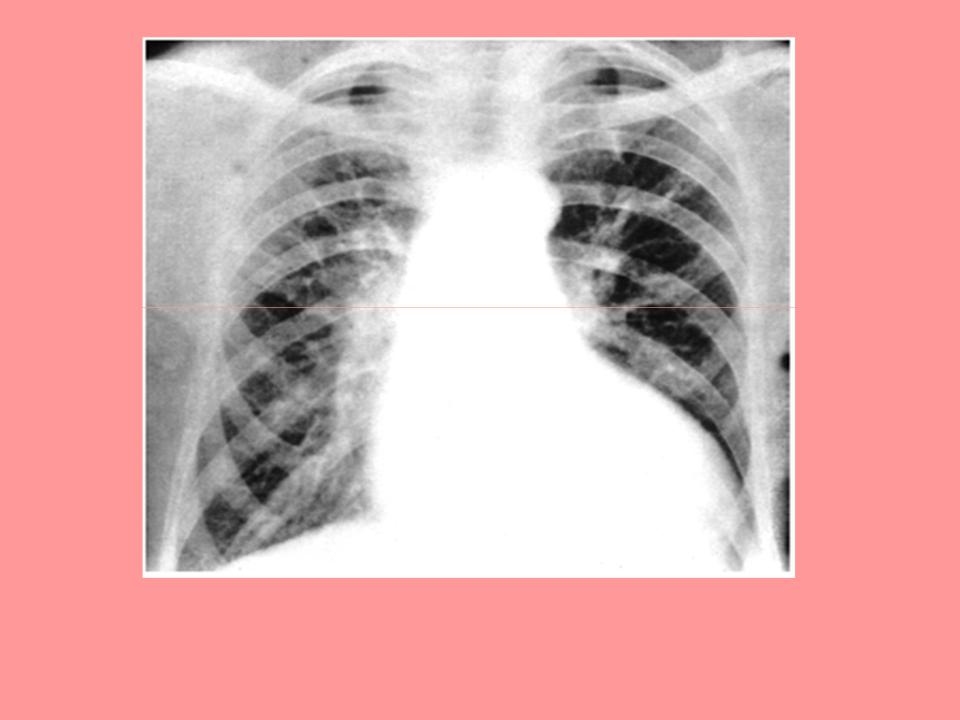

Рентгенограмма больного с недостаточностью клапана аорты и выраженной дилатацией ЛЖ при исследовании в прямой проекции

Рентгенография:

увеличение тени сердца влево

аортальная конфигурация сердца

расширение тени аорты

усиленная пульсация сердца и аорты